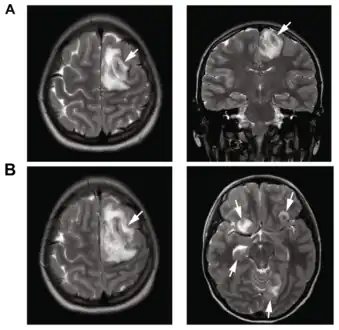

- Image of granulomatous amoebic encephalitis caused by Acanthamoeba

- A: T2-weighted MRI showing liquefied, necrotic brain tissue as a result of GAE caused by Balamuthia mandrillaris

B: T1-weighted MRI showing expansion and addition of necrotic areas 4 days later